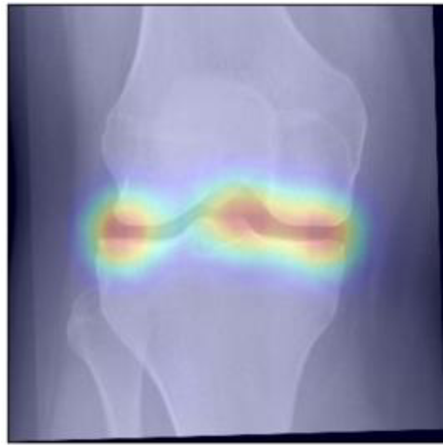

To gain insight into the basis of the CNN’s prediction, we used the GradCAM [24] approach and visualized the attention maps for the well-predicted knees. Examples of attention maps are presented in Figure 5. We observed that in various cases, the CNN paid attention to the compartment opposite to the one where degenerative change became visible during the follow-up visits. Additional examples of such attention maps are presented in Supplementary Figures 3, 4, 5 and 6.

Refer to caption

(a)

(b)

(c)

(d)

Figure 5: Examples of attention maps for progression cases and the corresponding visualization of progression derived using follow-up images from MOST datasets. Here, subplots (a) and (c) show the attention maps derived using a GradCAM approach. Subplots (b) and (d) show the joint-space areas from all the follow-up images (baseline to 84 months). Here, the subplot (b) corresponds to the attention map a) and the subplot (d) corresponds to the attention map (c).